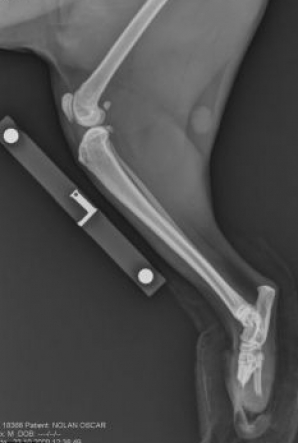

O pisica ,ale carei membre au fost taiate pe cale chirurgicala , a primit acum doua proteze, astefel cu ajutorul lor a nceput sa mearga din nou. Aceasta operatie a fost facuta in premiera de medicul veterinar Noel Fitzpatrick.Operatia poate fi vizualizata intr-un documentar facut de BBC numit "The bionic Vet"

Protezele intraosoase au fost confectionate de o echipa din londra de la University College , cu ajutorul profesorului Gordon Blunn.

"Ceea ce am reuşit să facem cu Oscar este să punem o bucată de metal şi o flanşă pe care pielea creşte ca pe un os mic", a declarat presei Fitzpatrick.